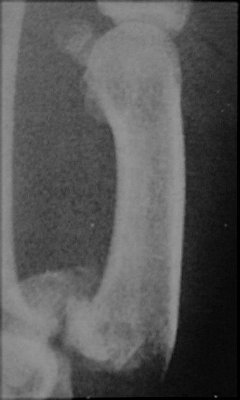

Return to Rolando Fracture